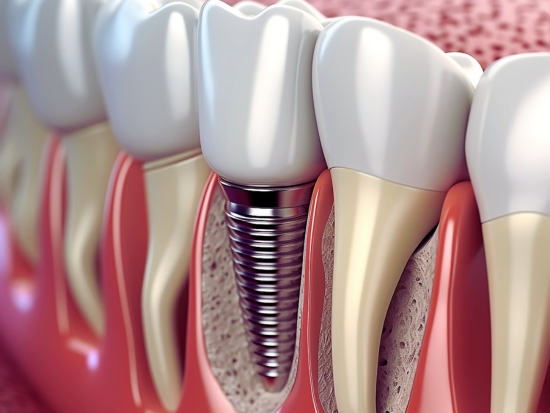

If all these seem like a battle that you can easily dodge, then take help of the implant dentistry. Dental implants offer a permanent solution for missing teeth. Implants restore your oral function and aesthetics without appearing fake. They look as natural as your regular teeth.

Implants are so in demand among patients with missing teeth because of their ability to integrate with the jawbone. They can even prevent jaw bone loss and ensure its stability.

Research shows dental implants can last decades with proper oral care. Other alternatives of missing teeth like dentures and bridges need frequent replacements to maintain their ideal functionality. Made from biocompatible titanium, implants fuse with the jawbone. They mimic natural tooth roots.

Tooth loss can turn your regular oral care routine fruitless due to the changing jaw bone structure. Losing a tooth can make the bone at its place attenuated. It can also shift the teeth around the lost tooth toward the new gap. If you want to get rid of all such complications, dental implants have your back! They stimulate jaw bone growth and prevent further bone loss. When your jawbone remains in a solid shape, your facial structure remains fine. It helps you prevent a sunken appearance.